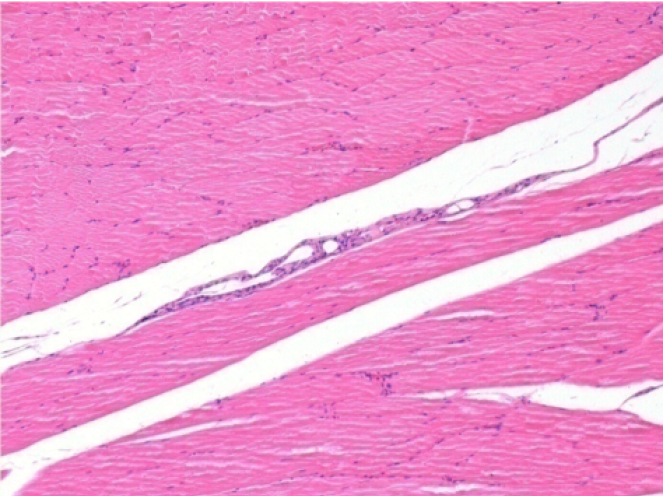

7 months after Endopeel Injection

7 months (D210)after Endopeel IM Injection 0.1ml in the right pretibial muscle.

Complete Restitutio ad integrum after 7 months

L : Control-100xD210

R:100xD210

L :Control 50xD210

R50X-D210